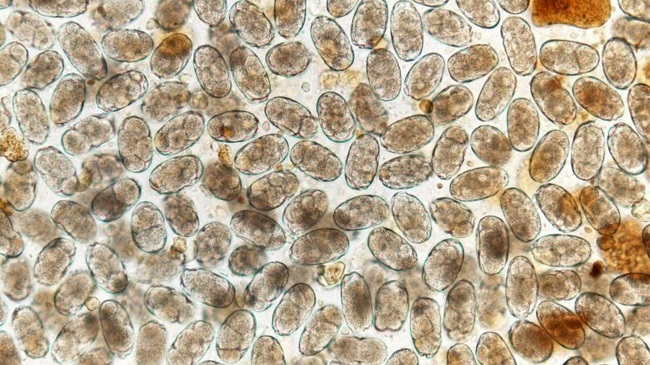

The parasites were shown to be highly prevalent in the breed after the researchers analyzed fecal samples from greyhound adoption kennels, three veterinary practices that interact with adoption groups, and an active racing kennel. Hookworms were found in four out of every five greyhounds tested. The one dog that tested negative could also have hookworms, but they could have been hiding in the tissues. It is known that hookworms can “hide” in tissues, where they will not proliferate or shed eggs until the infection develops and the infection spills into the dog’s intestines.

Almost all of the fecal samples tested positive for the mutation that allows hookworms to survive treatment with benzimidazoles, a broad-spectrum class of dewormers used in both animals and people, according to the researchers.